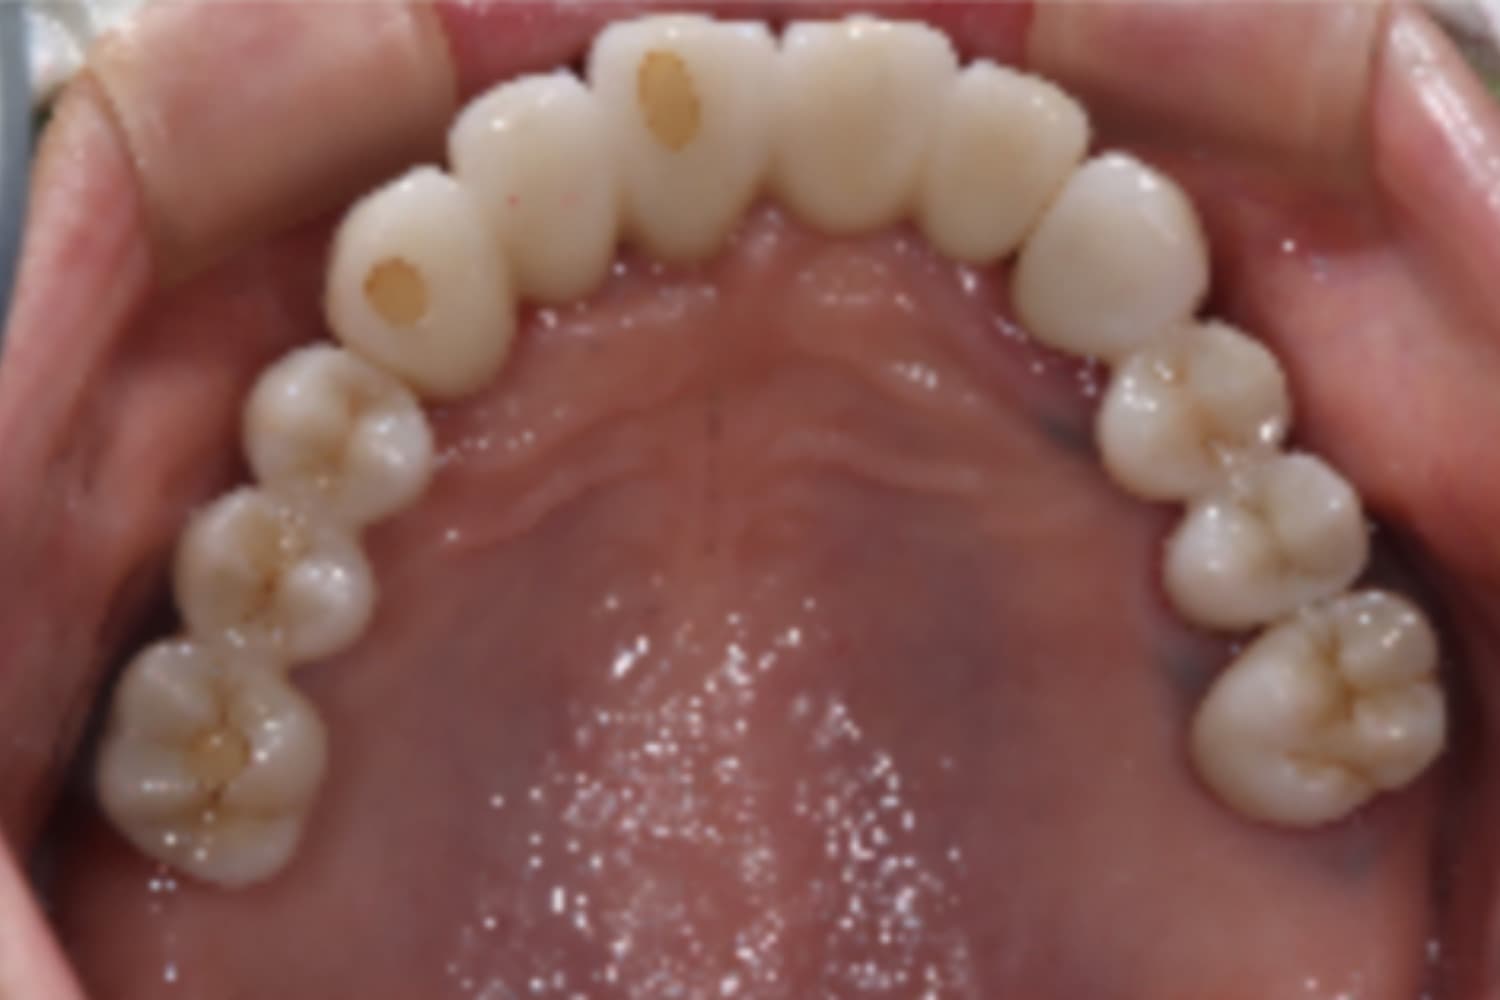

上顎欠損部のインプラント治療

Before

After

上顎欠損部にインプラントを行い、上顎前歯にはセラミックを装着

主訴

物が噛みづらい

治療期間

26カ月

治療回数

26回

費用

3,360,000円

副作用・リスク

・上顎洞炎を発症する可能性がある